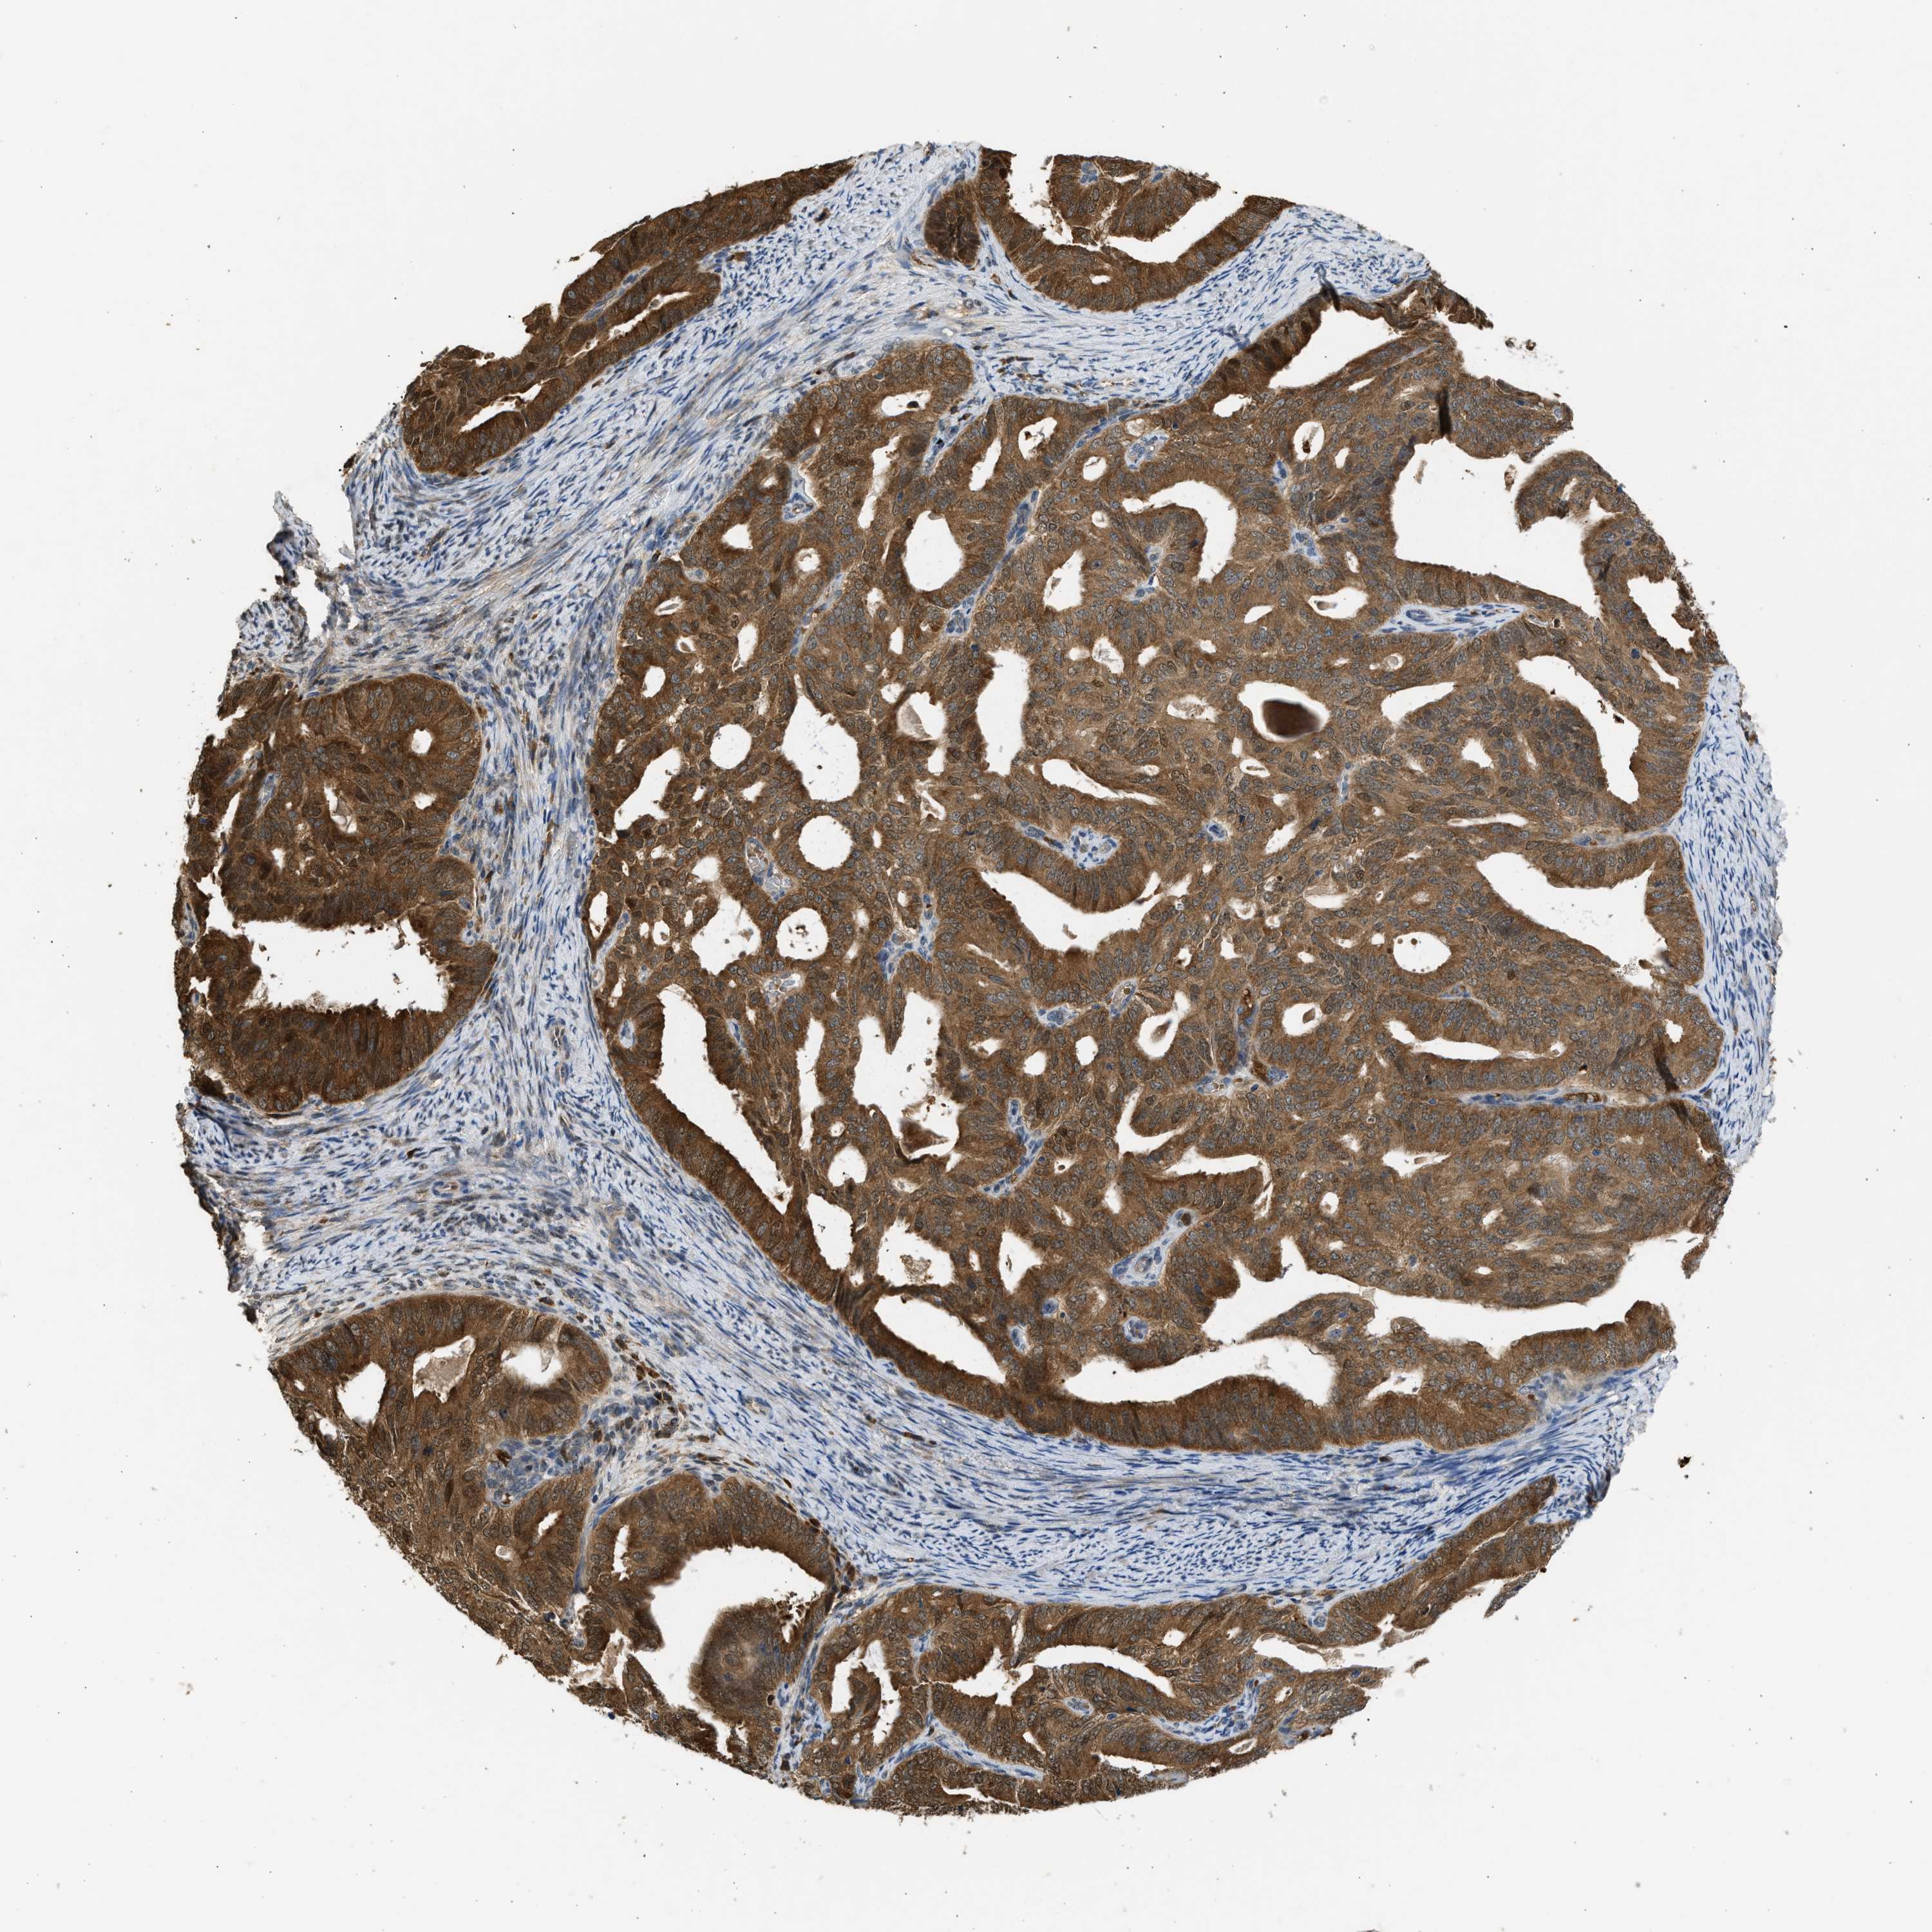

ENDOMETRIAL CANCER - Protein expressioni

A mouse-over function shows sample information and annotation data. Click on an image to view it in a full screen mode. Samples can be filtered based on level of antibody staining by selecting one or several of the following categories: high, medium, low and not detected. The assay and annotation is described here.

Note that samples used for immunohistochemistry by the Human Protein Atlas do not correspond to samples in the TCGA dataset.

Antibody stainingi

Antibody staining in the annotated cell types in the current human tissue is reported as not detected, low, medium, or high, based on conventional immunohistochemistry profiling in selected tissues. This score is based on the combination of the staining intensity and fraction of stained cells.

Each image is clickable and will lead to virtual microscopy that enables deeper exploration of all samples and also displays staining intensity scores, fraction scores and subcellular localization as well as patient and tissue information for each sample.

Antibody CAB018561

Staining

High

Medium

Low

Not detected

Intensity

Strong

Moderate

Weak

Negative

Quantity

>75%

75%-25%

<25%

None

Location

Nuclear

Cytoplasmic/membranous

Cytoplasmic/membranous,nuclear

Adenocarcinoma, NOS